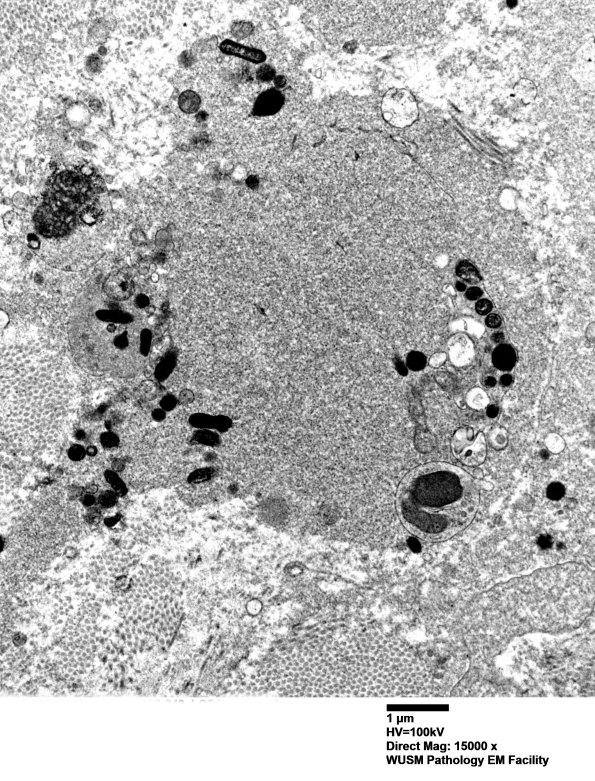

Higher magnification of image #12E5. (electron micrograph)